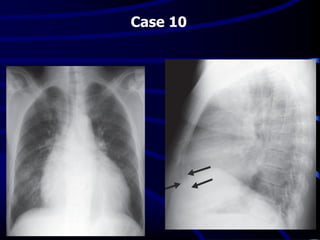

Case 10

A 47-year-old man presented with chronic renal

failure and dyspnea•

What is the MOST

LIKELY diagnosis?

A. Lobar pneumonia.

B. Primary lung cancer.

C. Acute heart failure.

D. Anterior mediastinal mass.

E. Pericardial effusion.